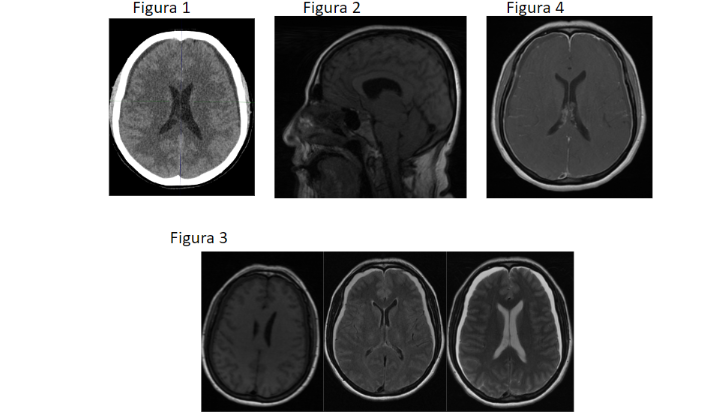

FIGURA 1: TC de cráneo sin CIV. Colecciónes extraxiales hemisféricas de atenuación similar al LCR.

FIGURA 2. RM Sagital 3DT1: Descenso caudal de 9mm amígdalas cerebelosas y del tronco del encéfalo por el agujero magno visualizando alteración en la morfología de la joroba de la protuberancia.

Engrosamiento hipofisario.

FIGURA 3. RM Axial T1, T2 y FLAIR: Colecciones extraxiales, hiperintenso respecto al LCR en T1,hiperintensas en T2 y FLAIR, de espesor máximo 8mm, compatibles con

hematomas subdurales crónicos.

FIGURA 4. RM Axial T1 C+: Captación paquimeníngea supratentorial.